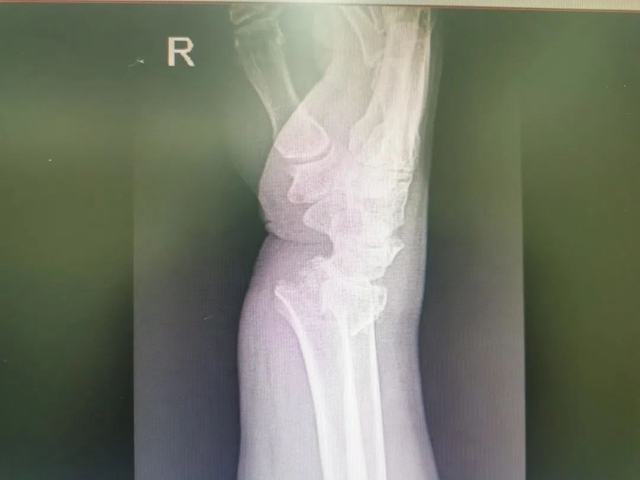

值守石棉县人民医院的骨伤科·正骨组王振龙副教授、手外·儿骨·烧伤整形组贺智榆主治医师接到伤员后,立即对其情况进行了检查评估,右侧腕关节掌侧、背侧肿胀明显,呈“餐叉样”畸形,影像结果提示:右侧桡骨远端粉碎性骨折、右侧尺骨茎突骨折。

王振龙、贺智榆讨论后,决定为其行桡骨远端粉碎性骨折切开复位内固定术。